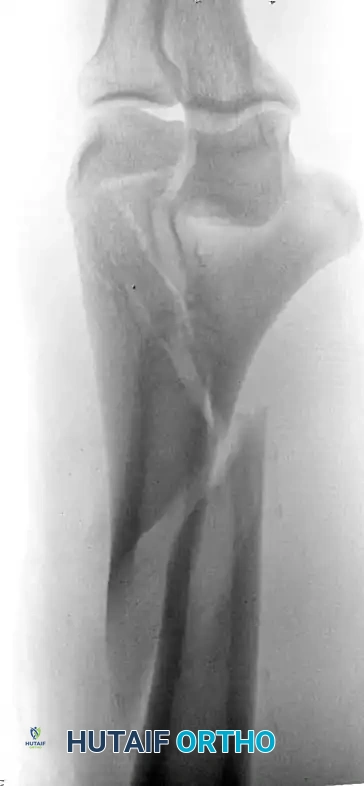

Isolated Column Fractures (AO/OTA Type B)

Lateral or medial column fractures can typically be reduced through a direct, localized approach. They are most effectively stabilized using a combination of interfragmentary lag screws and a minifragment buttress plate to resist shear forces.

Image

Fig. 2: Isolated lateral condylar fracture fixed with a lag screw and minifragment buttress plate.